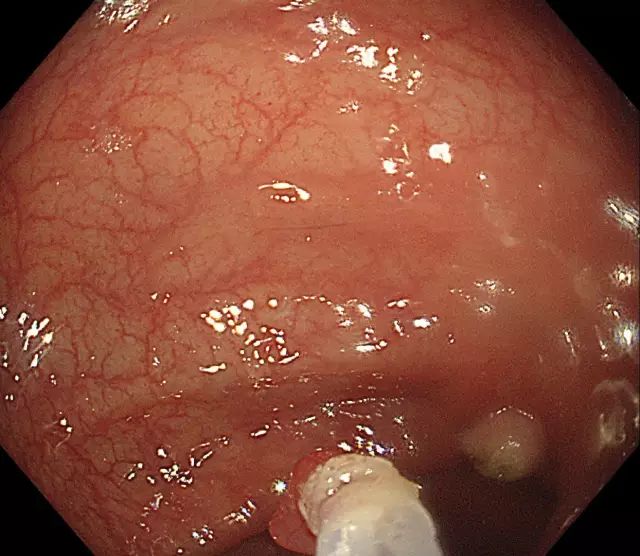

步骤一:发现息肉,并将其暴露于视野正中。

图片

步骤二:通过肠镜上的孔道插入特殊器械(电圈套器),并在息肉旁伸出钢丝圈。